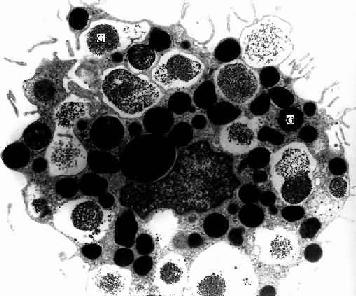

2.巨噬细胞 巨噬细胞(macrophage)是体内广泛存在的具有强大吞噬功能的细胞。在疏松结缔组织内的巨噬细胞又称为组织细胞(histiocyte),常沿纤维散在分布,在炎症和异物等刺激下活化成游走的巨噬细胞。巨噬细胞形态多样,随功能状态而改变,通常有钝圆形突起,功能活跃者,常伸出较长的伪足而形态不规则。胞核较小,卵圆形或肾形,多为偏心位,着色深,核仁不明显,胞质丰富,多呈嗜酸性,含空泡和异物颗粒,电镜下,细胞表面有许多皱褶、小泡和微绒毛,胞质内含大量初级溶酶体次级溶酶体吞噬体吞饮小泡和残余体细胞膜附近有较多的微丝微管(图3-5,3-6)。

猴巨噬细胞电镜像

图3-6 猴巨噬细胞电镜像×8400